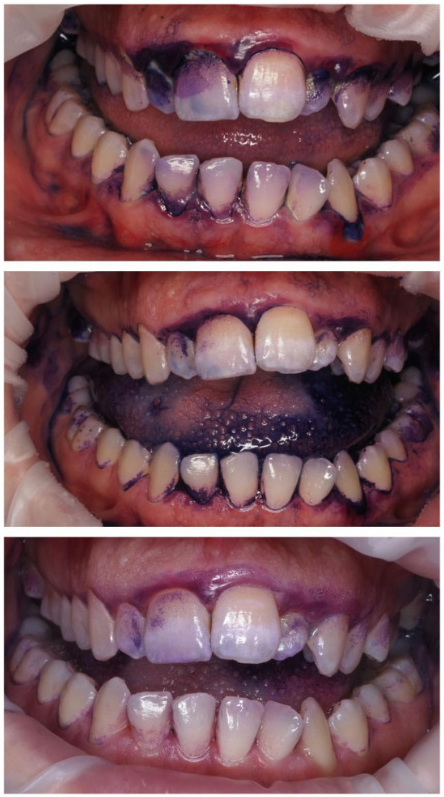

Pacjent zgłaszał się na regularne, co półroczne higienizacje. Wybarwienie płytki nazębnej na pierwszej wizycie ujawniło silne zaleganie płytki nazębnej dojrzałej, kwasowej, gęsto otaczającej zęby (kolor fioletowy). Z każdą kolejną wizytą widać było poprawę higieny i sukces działań higienistki stomatologicznej oraz motywacji własnej Pacjenta. Na trzeciej wizycie po wybarwieniu dostrzegalny jest już tylko delikatny, świeży biofilm. Dzięki technologii GBT posiadamy narzędzia do monitorowania higieny Pacjenta i pozytywnego wzmacniania jego dobrych nawyków.